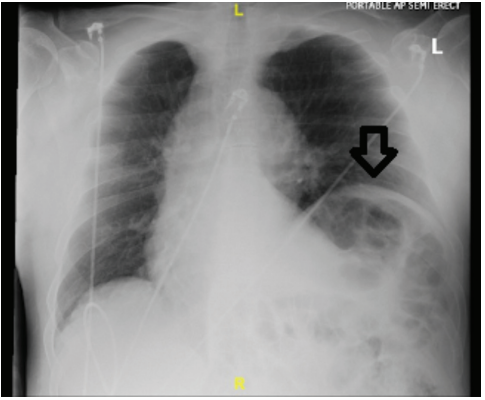

Due to symptoms consistent with unstable angina and a high pretest probability for CAD, a decision was made to take the patient to the cath lab the same day. Left heart catheterization was performed and showed patent coronaries. Prominent elevation of the left diaphragm was seen on multiple cine views with bowel visualization above the heart (Video). Transthoracic echo showed low normal ejection fraction but was otherwise unremarkable. Chest computed tomography (CT) angiography and chest x-ray were negative for pulmonary embolism and showed eventration of the left hemidiaphragm (Figures 1-3).